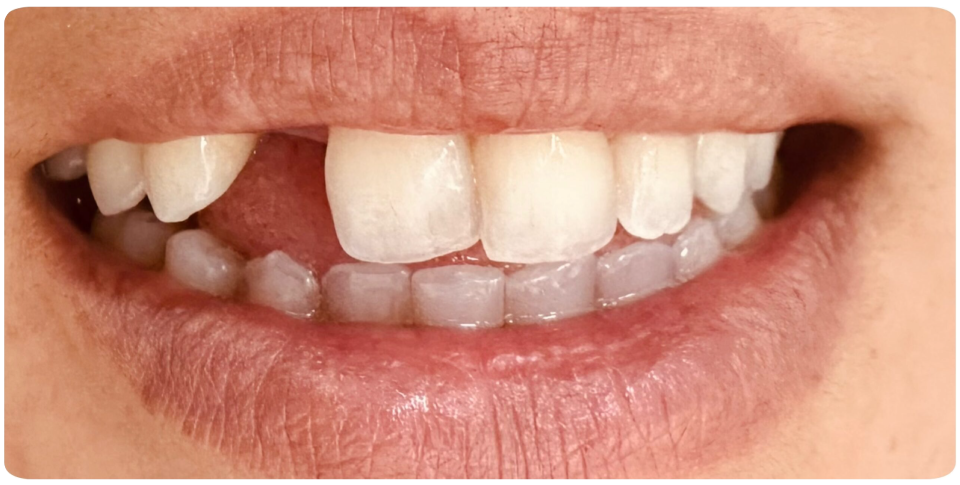

Implant Supported Bridge

An implant-supported bridge is an excellent solution for replacing multiple missing teeth without relying on natural teeth for support.

Instead of traditional bridges that require grinding down adjacent teeth, this option uses dental implants as a strong and permanent foundation.

- Stronger & More Stable – Provides better support and durability than traditional bridges.

- Preserves Jawbone Health – Prevents bone loss by stimulating the jawbone.

- No Damage to Natural Teeth – Adjacent teeth remain intact, unlike traditional bridges.

- Enhanced Function & Aesthetics – Restores chewing ability and a natural-looking smile.

Ideal for multiple missing teeth, implant-supported bridges offer a long-lasting and comfortable solution for restoring your smile.